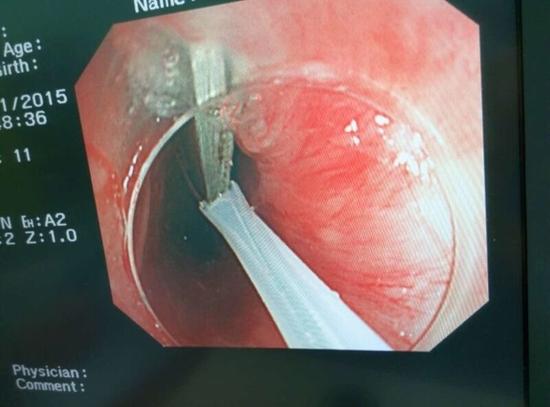

醫(yī)生從華先生胃里取出的鑷子和打火機(jī)

手術(shù)中,范醫(yī)生通過(guò)胃鏡準(zhǔn)確發(fā)現(xiàn)了胃里的鑷子。但讓他驚訝的是,在華先生胃底竟然還躺著三個(gè)被腐蝕了的打火機(jī),打火機(jī)的金屬部件都已經(jīng)不見(jiàn)了。

隨后,范醫(yī)生先用圈套器套取出了長(zhǎng)10厘米的鑷子,再一個(gè)一個(gè)地取出了打火機(jī)。整個(gè)取出過(guò)程小心謹(jǐn)慎而又一氣呵成,只用了不到10分鐘。